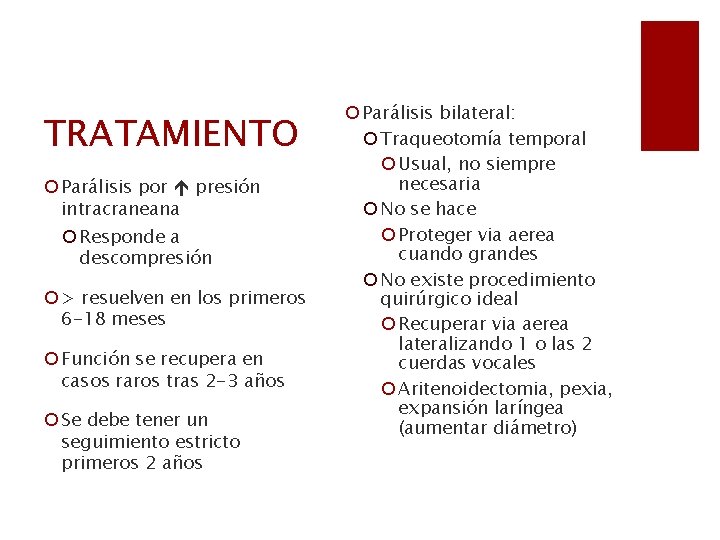

TRATAMIENTO ¡ Parálisis por presión intracraneana ¡ Responde a descompresión ¡ > resuelven en los primeros 6 -18 meses ¡ Función se recupera en casos raros tras 2 -3 años ¡ Se debe tener un seguimiento estricto primeros 2 años ¡ Parálisis bilateral: ¡ Traqueotomía temporal ¡ Usual, no siempre necesaria ¡ No se hace ¡ Proteger via aerea cuando grandes ¡ No existe procedimiento quirúrgico ideal ¡ Recuperar via aerea lateralizando 1 o las 2 cuerdas vocales ¡ Aritenoidectomia, pexia, expansión laríngea (aumentar diámetro)